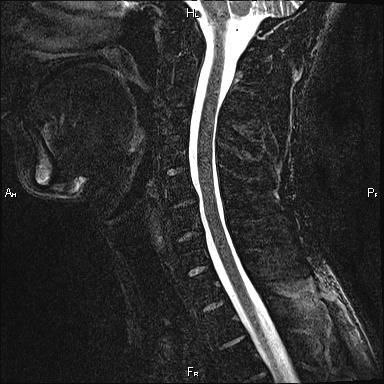

Azt kell tennie, az MRI-t a nyaki gerinc, széf (nincs sugárzás), fájdalommentes vizsgálat által előállított mágneses mező egy képet a gerinc és a gerincvelő. MRI nagyon jól látható az idegek és a porckorongok.

A mi központtól, a betegnél műtét '31 a diagnózis nyaki osteochondrosis. Sérv m / n disk C5-C6 maradt. Fájdalom a bal karját.

Sebészet lefolytatott: sérv m / n C5-C6 lemezt bal parafaringialnogo hozzáférést. Discectomy C5-C6. Szerelési Pikovsky interbody ketrec (statikus protézis) m / n C5-C6 disk.

A műtét után a fájdalom a bal ruke.Patsient lemerült regresszió neurológiai tünetek.